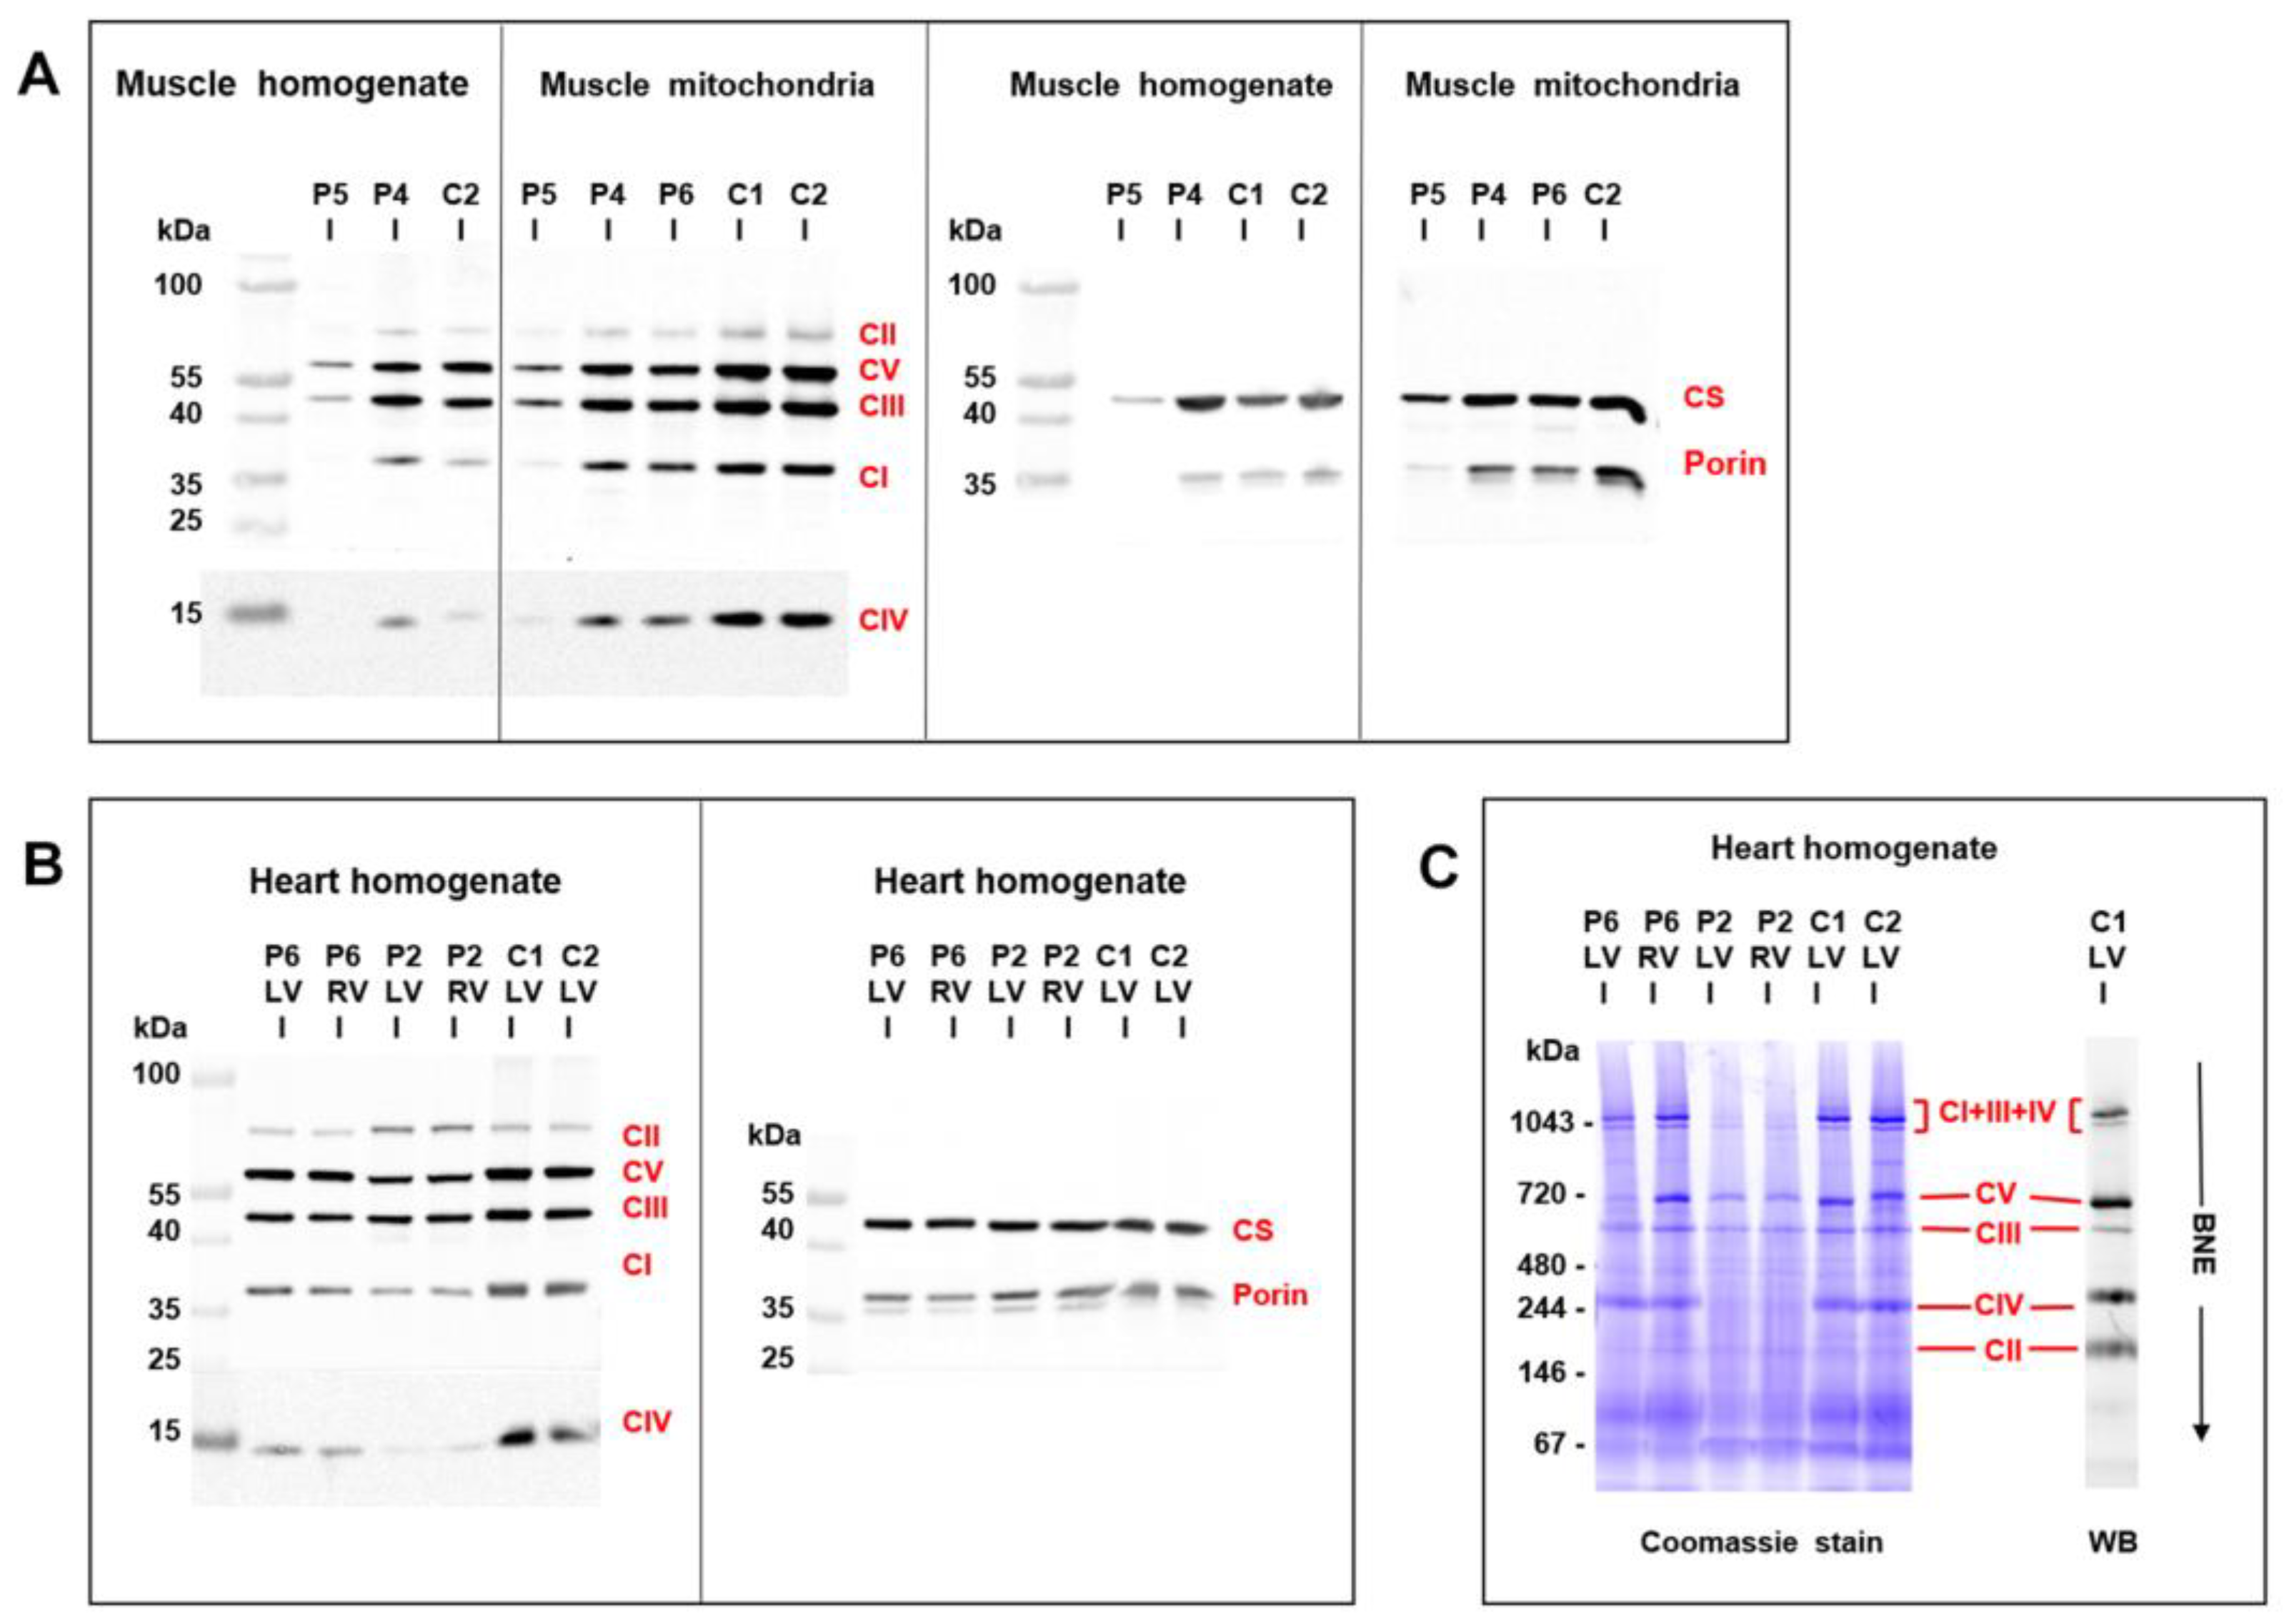

3.5. Mitochondrial Function and Content in Skeletal Muscle and Heart